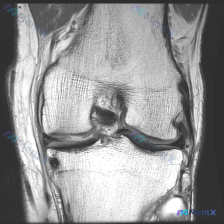

刚整理了一个很有临床意义的病例,核心矛盾是「临床怀疑软骨异常,但现有影像完全正常」,把整个分析思路分享给大家。 病例基础信息 这是一份单张膝关节矢状位T1加权MRI影像,临床提出的核心观察方向是「软骨异常」,无其他临床病史、症状或其他检查资料。 影像具体观察结果 我们先把影像所见说清楚: 1. 骨骼...

看到这个病例挺有代表性的,整理出来和大家分享一下思路。 病例基础信息 这是一张膝关节矢状位T1加权序列MRI影像,用户提出问题:观察图像是否存在软骨异常。 先给大家整理影像评估的基本结果: 1. 骨骼结构:股骨远端、胫骨近端、髌骨皮质连续,骨髓信号未见异常高低信号,关节面形态基本正常 2. 半月板:...

今天整理了一个很有启发意义的读片病例,问题是临床怀疑膝关节软骨异常,只给了一张矢状位T1加权MRI,我们一起来梳理整个分析过程。 病例影像基础信息 这是一张膝关节矢状位T1加权像(T1WI),我们先把基础解剖评估说清楚: 1. 骨骼结构:股骨远端、胫骨近端骨皮质连续,无骨质破坏或骨折,关节间隙正常,...

病例基础信息 这是一份特殊的膝关节影像评估需求:输入描述提示存在软骨异常 (Chondral abnormality),提供1张膝关节矢状位MRI静态图像,我们先看影像学分析结果: 影像学观察结果 1. 骨骼与软骨:股骨远端、胫骨近端、髌骨骨皮质完整,无骨折,无骨髓水肿;股骨髁、胫骨平台、髌股关节面...

病例读片讨论:怀疑软骨异常,单张MRI却没发现问题,该怎么办? 这是一份膝关节矢状位T1加权MRI读片需求,核心疑问是排查软骨异常,我整理了完整的分析思路分享给大家。 一、影像基础信息 本次读片仅提供单张膝关节矢状位T1加权MRI图像: - T1序列中,骨髓脂肪呈高信号,液体、皮质骨、半月板等致密组...

拿到这个病例:核心问题是「这张膝关节MRI里的软骨异常在哪里?」,先把读片结果和思路整理给大家。 一、先整理读片基本信息 这是一张单张膝关节矢状位MRI,信号对比度提示更符合质子密度加权像(PDWI)或T2加权像(T2WI),不是典型T1加权像,层面在膝关节中线附近,可以清晰显示后交叉韧带。 逐结构...